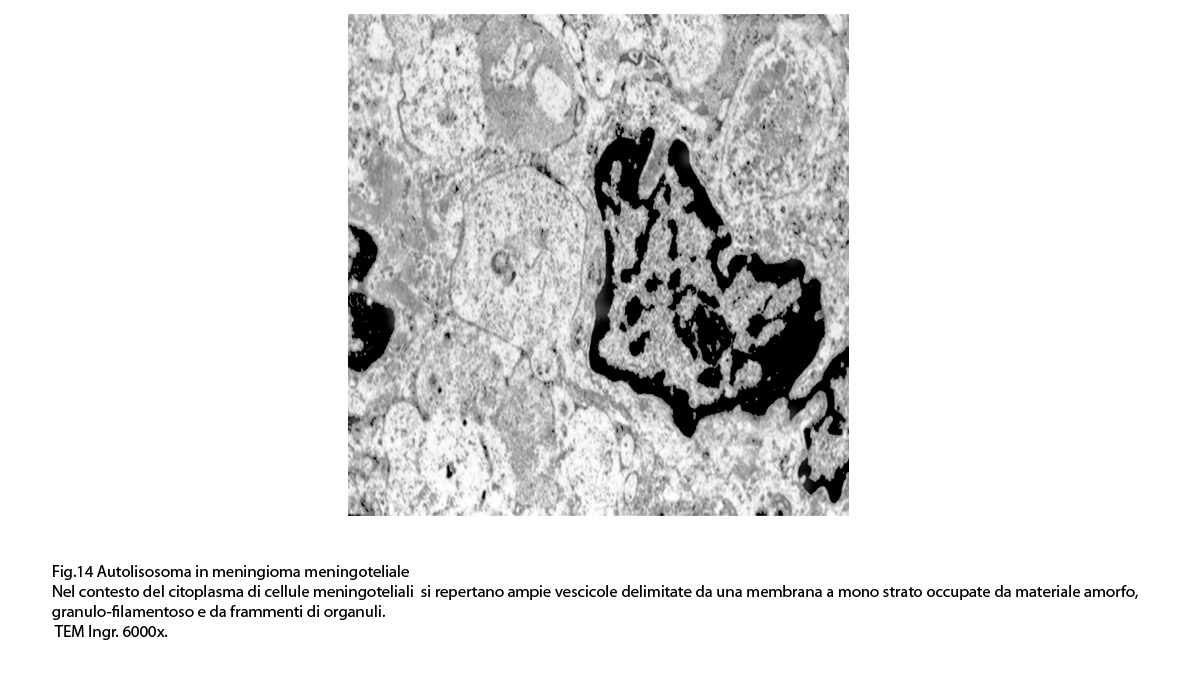

Alcune cellule meningoteliali sono sedi, sopratutto a livello delle fasce periferiche, di ampie vescicole, di forma irregolare le quali sono demarcate da una membrana a mono-strato; gli spazi di queste vescicole sono in buona parte occupati da materiale amorfo, da frammenti filamentosi e da organuli intracitoplasmatici,tutto sottoposto a degradazione.

E’ possibile anche il reperto di elementi cellulari aventi il citoplasma occupato da ampie vescicole,delimitate da una membrana a monostrato, le quali sono ricolme di materiale amorfo,da strutture granulo-filamentose o da frammenti di organuli.